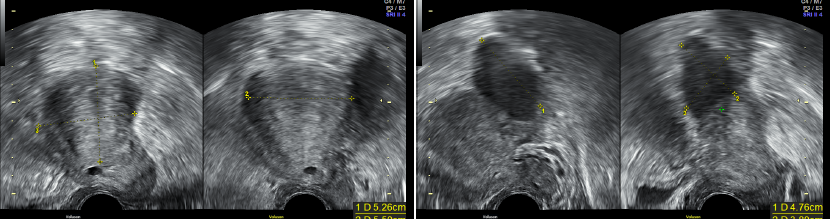

患者,刘某,28岁,G0P0,因“发现左附件肿物3年,痛经进行性加重3月”于2022年2月就诊于北京清华长庚医院妇科。 现病史: 患者平素月经规律,4-5/28天,量中,继发性痛经(+),LMP:2022.01.15。患者8年前开始痛经,可忍受,VAS评分2-3分,偶需服药,痛经时伴恶心、腹泻,无尿频尿急,3年前就诊我院,妇科彩超提示子宫腺肌症、双卵巢非纯囊性包块,右侧大小约2.7cm×2.2cm,左侧大小约4.4cm×3.0cm;盆腔核磁提示:子宫腺肌瘤;双侧巧克力囊肿,左侧较大;右侧输卵管积水?查CA-125:181.5 U/ml,建议手术治疗,患者考虑近期生育,予以口服中成药对症治疗,效果欠佳。近3月患者出现痛经加重,口服止疼药逐渐加量至经期每天2片,VAS评分6分。2022年2月复查彩超提示左卵巢大小7.5cm×5.7cm×5.6cm,内可见非纯囊性包块,大小约6.4cm×5.0cm×4.9cm,内可见密集光点回声,建议手术治疗,门诊以“左侧卵巢囊肿、子宫腺肌症”收入院。 既往史: 2017年因外伤行颅骨骨折手术。余(-) 月经婚育史: 月经初潮14岁,4-5/28天,量多,痛经中重度,需口服止疼药。已婚,G0P0,有生育计划。 家族史: 无特殊 专科查体: 外阴(-); 阴道:已婚未产型,分泌物不多; 宫颈:光,触血阴性; 子宫:前位,稍增大,无压痛; 三合诊:左侧附件区可触及一囊性肿物,直径约6cm,活动度差,压痛(-),右附件区未及明显异常,子宫直肠陷凹可及触痛结节,直径1cm。 辅助检查: TVS(2019-1-20,我院): 子宫前位,大小6.3cm×6.1cm×4.9cm,形态饱满,轮廓尚规整,肌层增厚回声不均匀,内可见多发短线样强回声,后伴栅栏样声影,以后壁为著,前壁厚约1.3cm,后壁厚约4.5cm。子宫内膜厚0.7cm,回声均匀。 右卵巢大小2.4cm×2.3cm×2.1cm,内可见非纯囊性包块,大小约2.7cm×2.2cm,内可见密集光点回声,囊壁可见血流信号。左卵巢大小7.6cm×5.4cm×4.8cm,内可见非纯囊性包块,大小约4.4cm×3.0cm×3.9cm,内可见密集光点回声,囊壁可见血流信号。[超声提示]:子宫腺肌症,双卵巢非纯囊性包块。 2019-1-16 CA125 181.5U/ml 2019-1-25 盆腔核磁提示:子宫腺肌瘤;双侧巧克力囊肿,左侧较大;右侧输卵管积水? TVS(2022-1-19,我院): [超声所见]:子宫前位,大小5.6cm×6.3cm×5.7cm,形态饱满,轮廓尚规整,肌层增厚回声不均匀,内可见多发短线样强回声,后伴栅栏样声影,以后壁为著,前壁厚1.0cm,后壁厚4.3cm,子宫内膜厚0.6cm,回声均匀。右卵巢大小3.3cm×2.4cm×1.8cm。左卵巢大小7.5cm×5.7cm×5.6cm,内可见非纯囊性包块,大小约6.4cm×5.0cm×4.9cm,内可见密集光点回声,囊壁可见血流信号。[超声提示]:子宫腺肌症,左卵巢非纯囊性包块。 2022-1-23 CA125 217.4U/ml AMH:2.07mg/ml